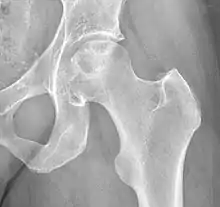

Hip replacement

When patients have later stages of ONFH most other treatment options are not successful or even worth trying. Thus the only option is total hip replacement where the FH and the pelvic portion of the joint are both replaced, or one part of the hip joint is replaced. Many surgeons do choose to just replace the hip altogether in some mild cases because hip replacements have a longer success rate and most of the time if you try to do partial replacements or FH sparing techniques that are not totally successful: later in life a hip replacement is needed. A lot is needed to take into consideration including age and progression.[3]